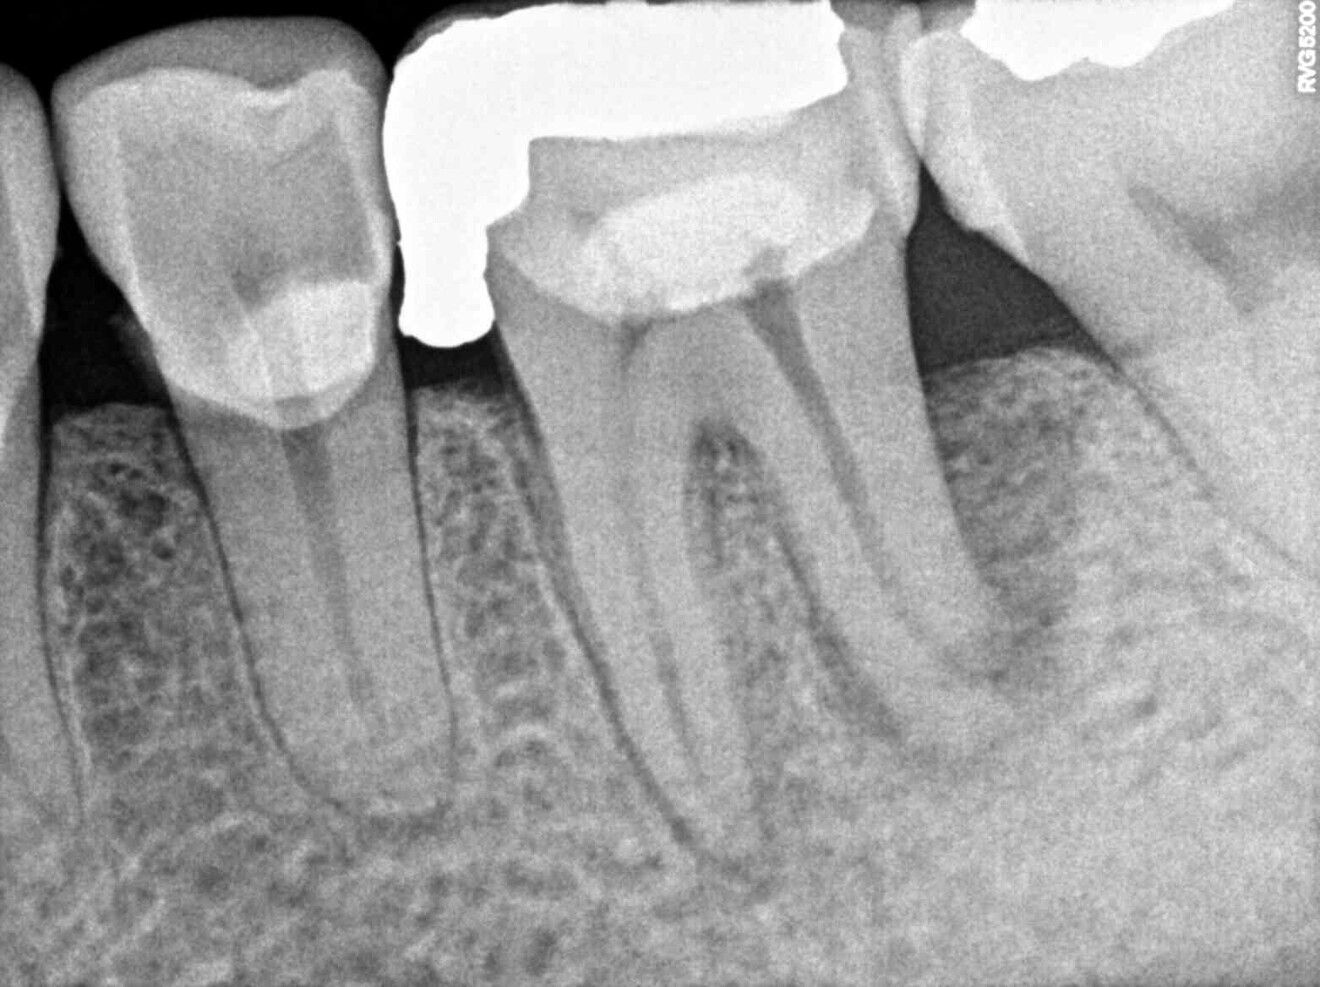

Upon this finding, the hemisection procedure was discussed with the patient, and he gave his full consent to perform it. Initially, the distal canal was gently irrigated with sodium hypochlorite at a 5% concentration and the canal medicated with calcium hydroxide (Fig. 3). At a second appointment 15 days later, the buccal abscess had receded (Fig. 4). The mesial root canal was then treated conventionally, determining the working length with an electronic apex locator (Root ZX II; Morita), performing instrumentation with nickel–titanium files (Pro-Flexi Files, Denco) and obturating with gutta-percha and a bioceramic sealer using the single-cone technique (CeraSeal, Meta Biomed). A resin core was placed with a dual-polymerising composite (CompCore AF, Premier Dental; Figs. 5 & 6).

One year later, the restoration was performing well and the patient was asymptomatic. Radiographs and a CBCT control scan showed complete bone healing. On the periapical radiograph, the tooth showed a healthy periodontal ligament and no signs of failure in the restoration (Fig. 12). The cross-sectional, axial and coronal views of the CBCT scan showed good bone width and height and no pathological findings (Figs. 13–16). The oclusal scans and clinical images showed good adaptation of the new restoration and a healthy gingiva (Figs. 17–20).